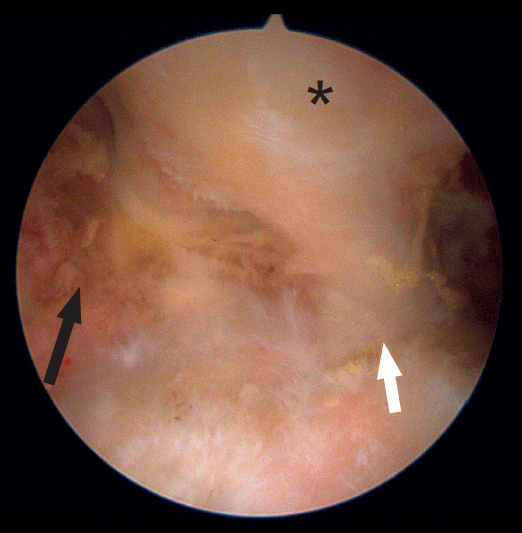

The femoral quadriceps is traditionally considered to be composed of four muscles: the rectus femoris (RF), vastus medialis (VM), vastus lateralis or externus (VE) and the vastus intermedius. However, a number of recent anatomical studies have described different variants of normal, with individuals presenting from 5 to 8 muscle heads(7). Of these, the RF is the only biarticular muscle; thus, in addition to conforming the primary flexor muscle group of the hip, it also extends the knee joint and is exposed to a risk of elevated elongation if movements of both are combined. Due to this characteristic, its length, tendency to perform eccentric-type contractions, and its high percentage of type II fast-twitch fibres, the RF is the quadriceps component most often affected by injuries. Mention also must be made of its complex proximal origin(8), with a direct tendon originating in the anterior inferior iliac spine and a second indirect (or reflected) tendon that originates in the supra-acetabular groove (Figure 2). At approximately 2 cm below their origin, both tendons form a combined tendon structure. The direct portion mainly contributes to the superficial component of the combined tendon and merges with the anterior aponeurosis or fascia of the muscle. In contrast, the indirect portion contributes to the fibres of the deep intramuscular component of the combined tendon and forms a deep musculotendinous junction that extends distally, approximately encompassing the two proximal thirds of the length of the muscle belly of the RF. This deep intramuscular tendon is initially located medially and is "comma" shaped (Figure 3). Distally, the tendon flattens out and becomes linear in shape with a sagittal long axis, and is located more laterally within the muscle(9). This central tendon (also called central aponeurosis or intramuscular septum) in turn gives rise to the muscle fibres that confer the bipennate appearance of this muscle. In turn, the direct tendon gives rise to a superficial expansion that anteriorly covers the proximal part of the muscle, from which muscle fibres also emerge. All the muscle fibres insert in the posterior aponeurotic expansion (posterior fascia) located on the dorsal surface of the muscle, which distally forms the anterior layer of the quadriceps tendon. In this way we have a bipennate structure originating from the central tendon, which differs from another surrounding structure originating from the superficial expansion and which is unipennate. This type of configuration has been referred to as a "muscle within a muscle"(10).

Figure 2. Endoscopic view of the tendon of origin of the left rectus femoris. The optics are located anterior to the joint capsule of the hip (which occupies the floor of the image). Note the direct tendon (black arrow) originating in the anterior inferior iliac spine, the reflected tendon (white arrow) originating in the supra-acetabular region, and the combined tendon formed by the joining of the previous tendons (asterisk).